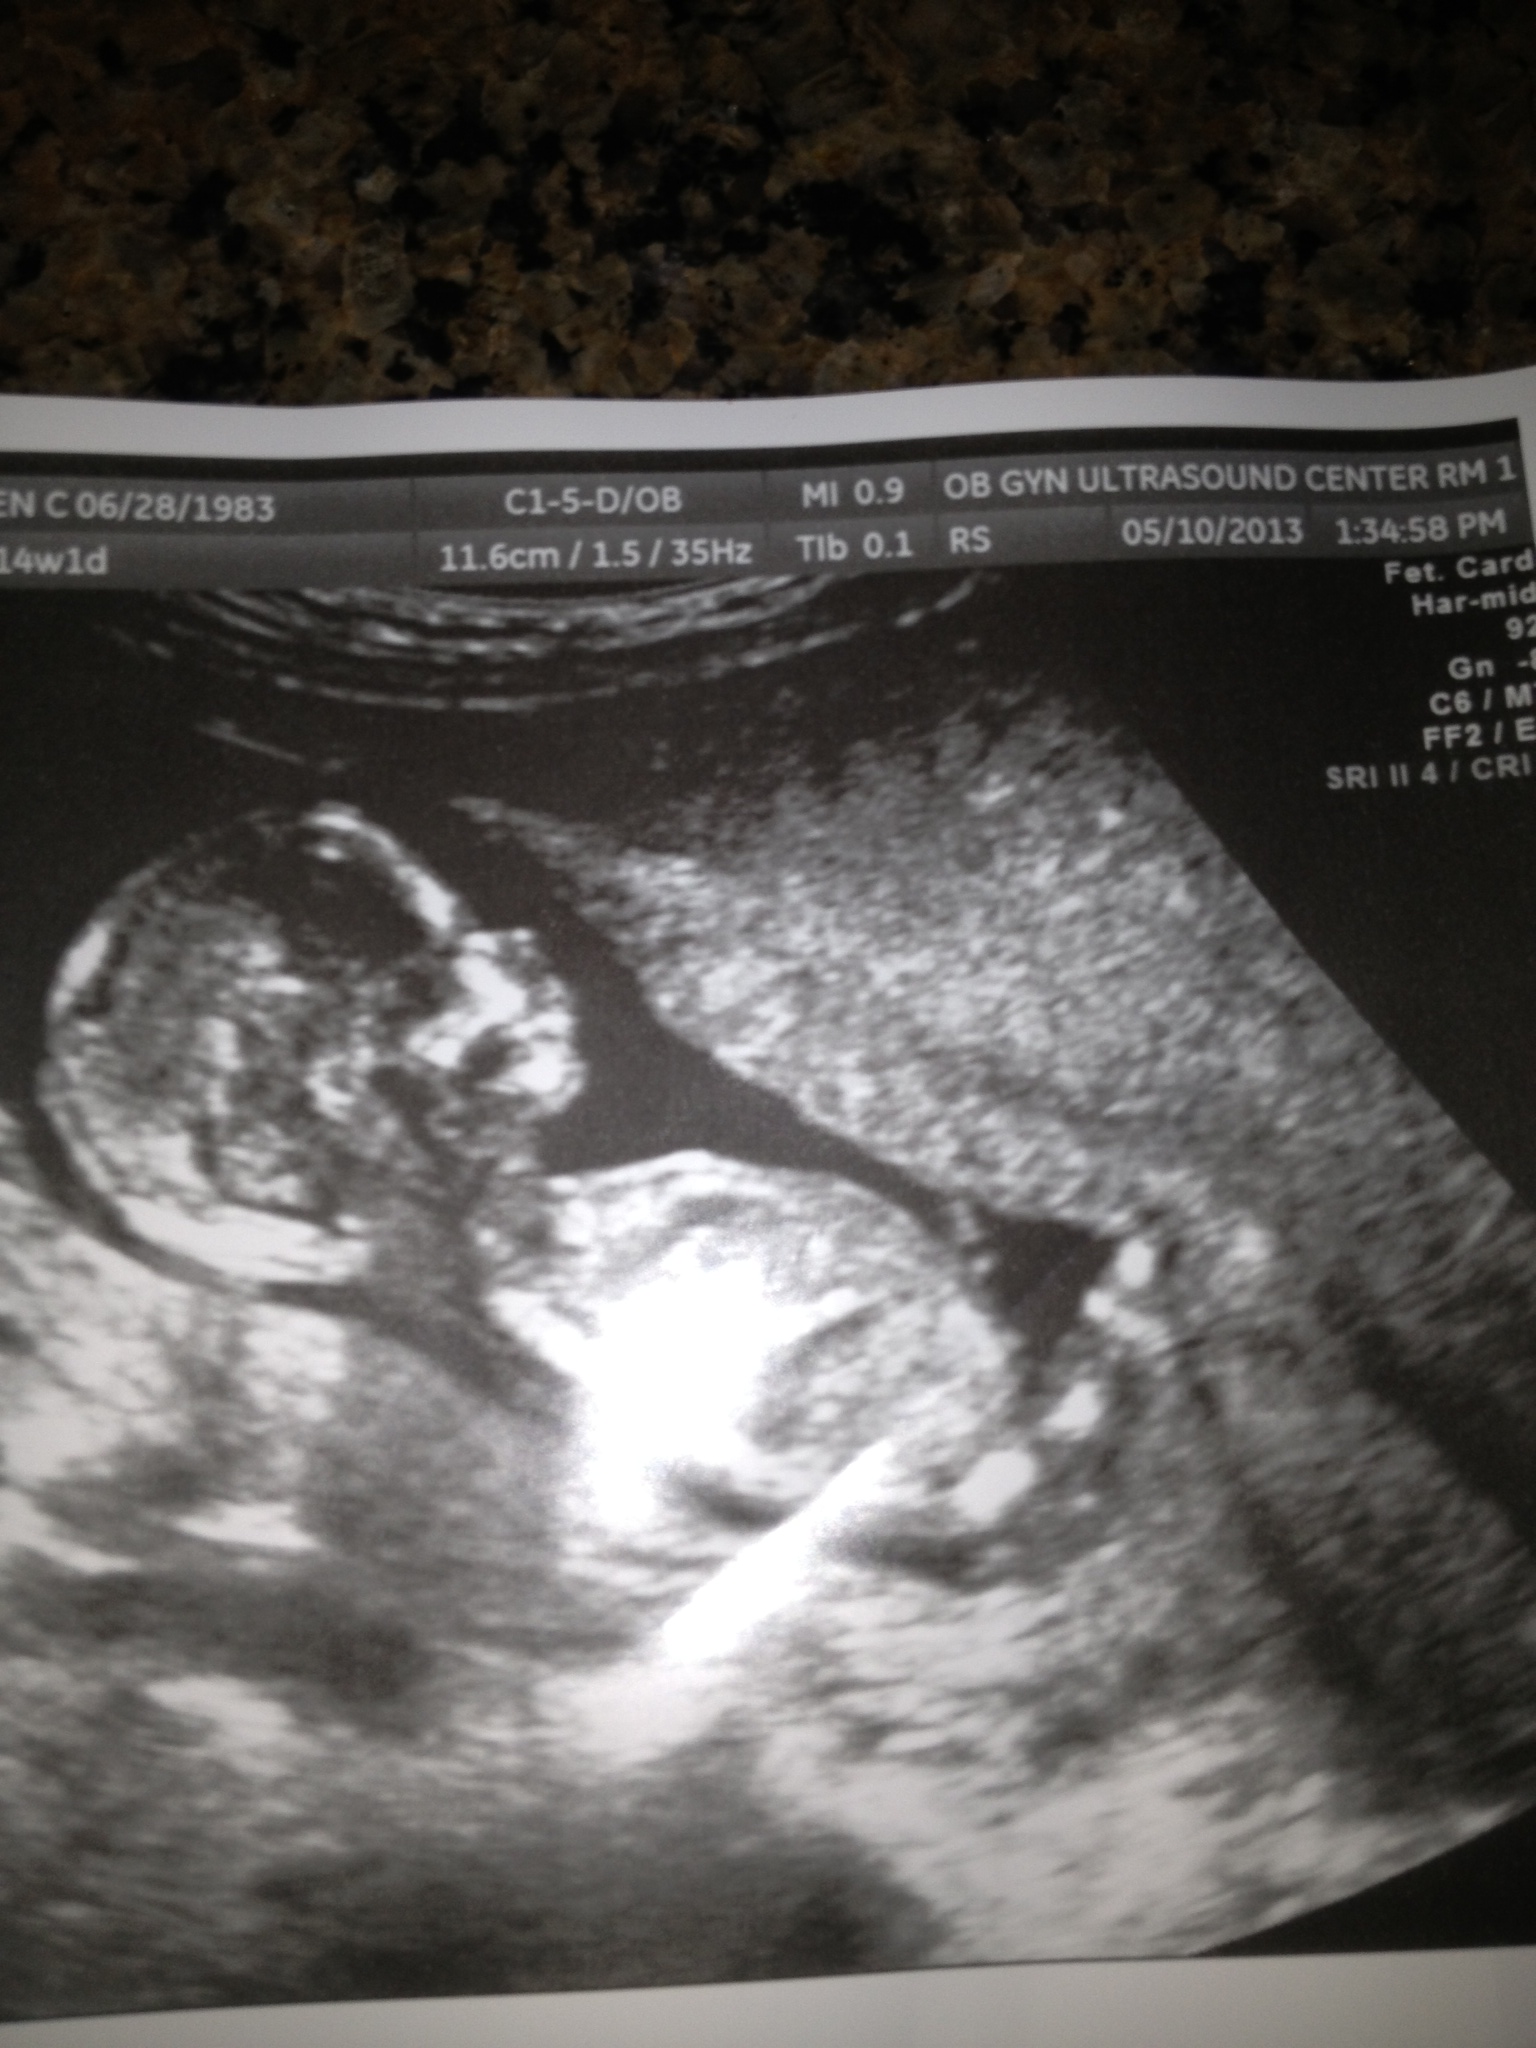

PINK OR BLUE???

What do you think?

I don't see any clues

Guessing girl :)